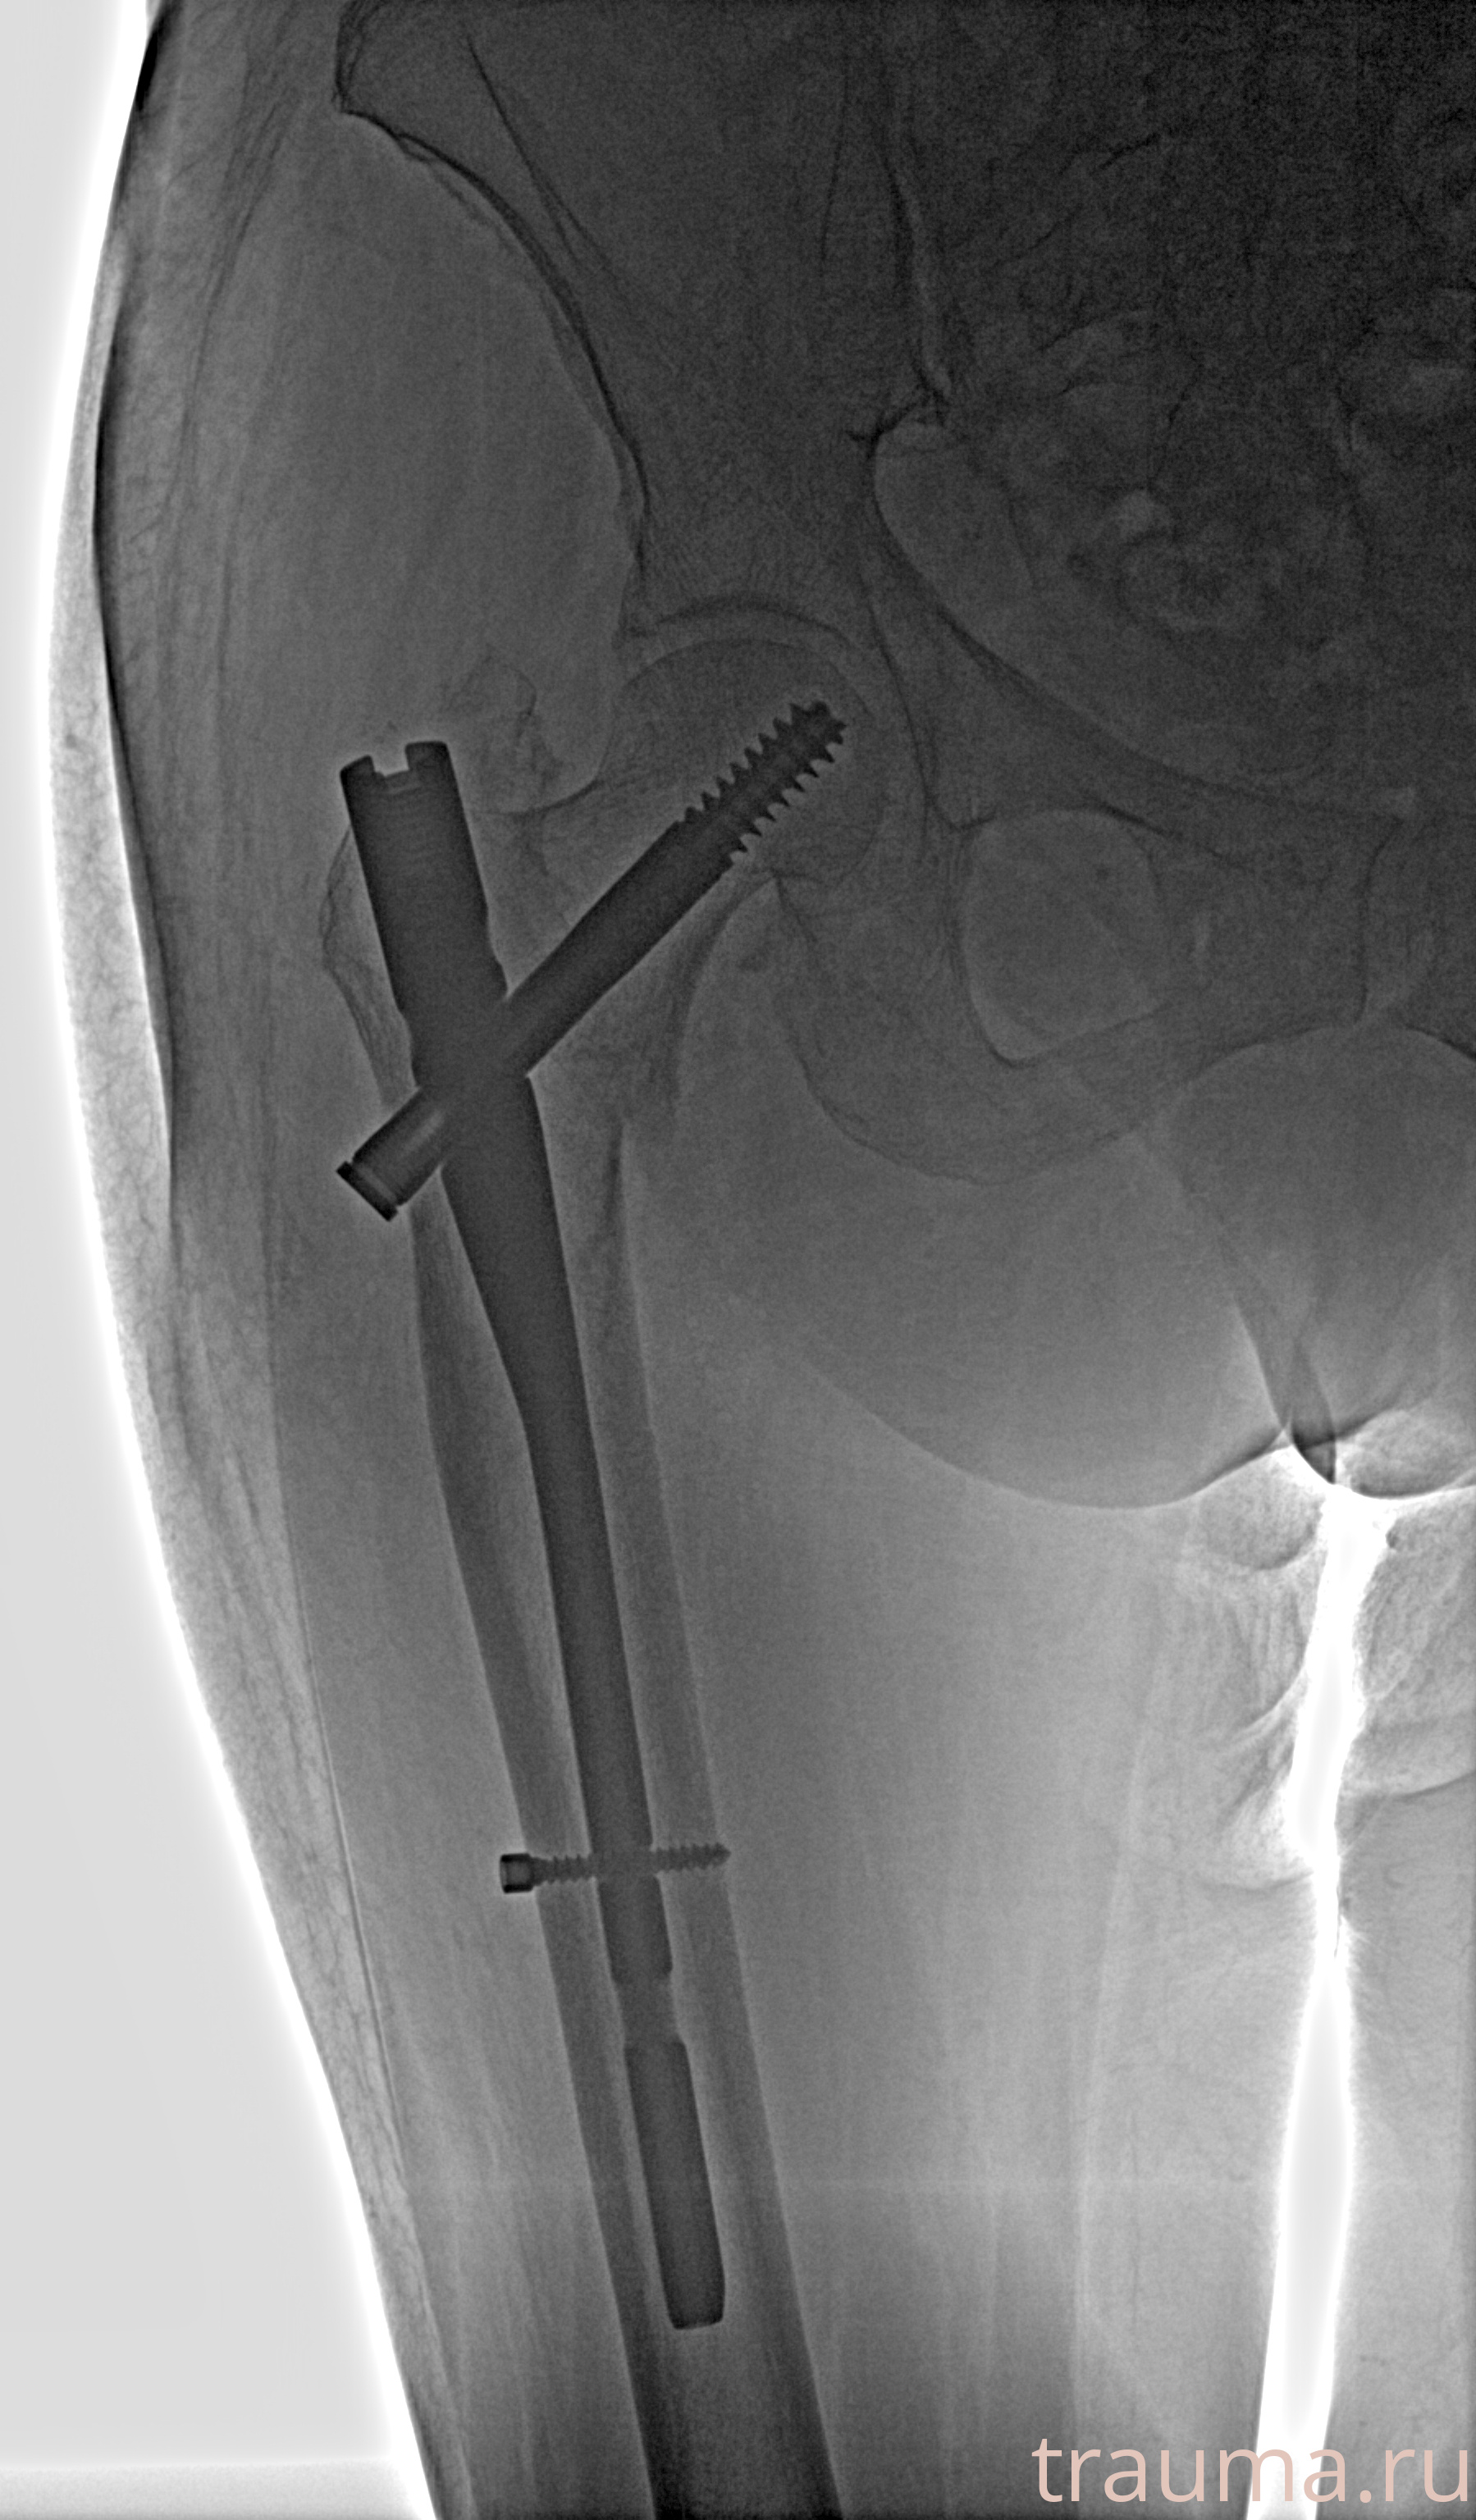

Рентгенограммы

Рентген на дому: по вашему адресу приезжает врач-рентгенолог, травматолог-ортопед с мобильным рентгеновским аппаратом, проводит диагностику травмы или заболевания, делает необходимые рентгенограммы, дает рекомендации по дальнейшему лечению. Получить качественные снимки в домашних условиях возможно благодаря уникальной методике, разработанной МосРентген Центром для института  Склифосовского